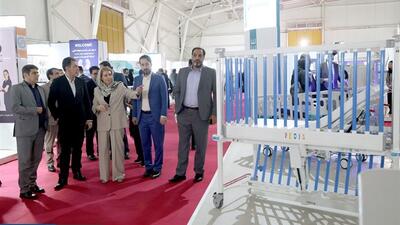

بازدید رئیس جمهور از نمایشگاه ایران هلث

دکتر مسعود پزشکیان رئیسجمهوری اسلامی ایران، صبح امروز سهشنبه از بیستوششمین نمایشگاه بینالمللی تجهیزات پزشکی، دندانپزشکی، دارویی و آزمایشگاهی (ایرانهلث) بازدید کرد.